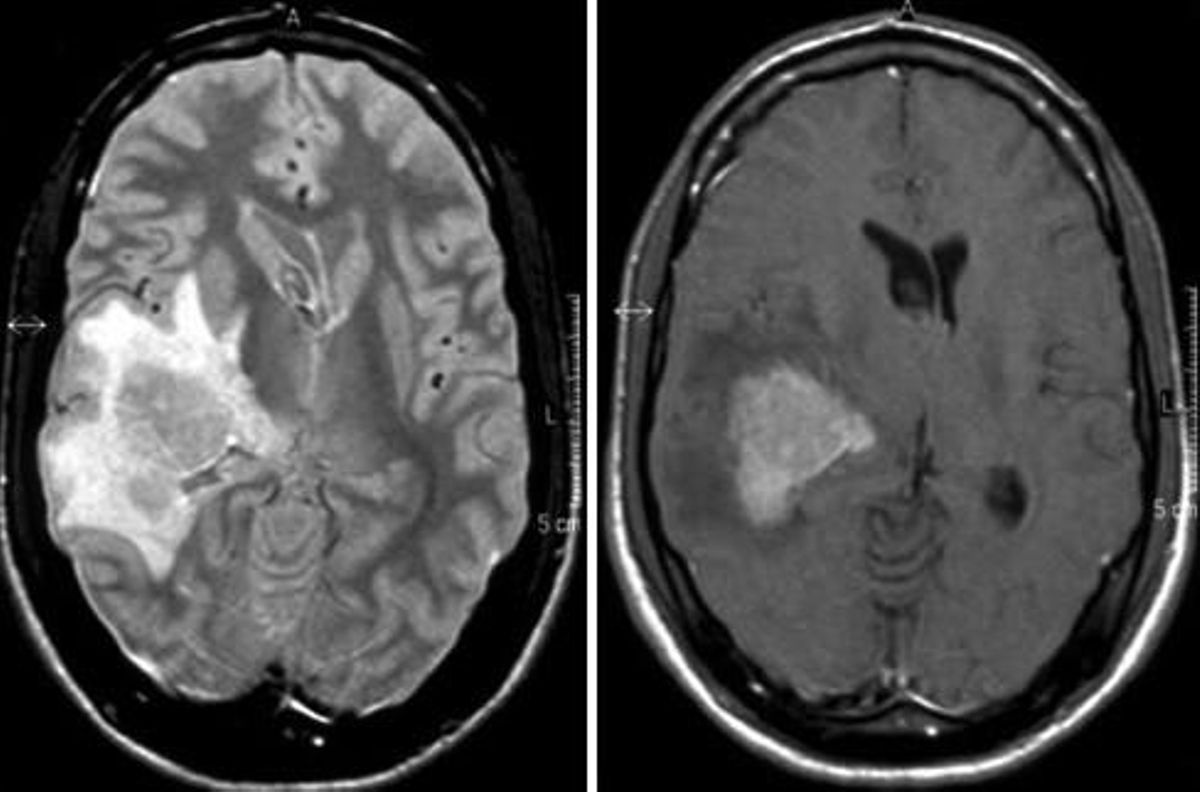

Linfoma cerebral, en una imagen de archivo / EPE